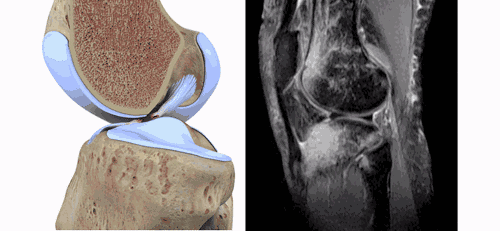

ACL损伤的间接征象:指ACL断裂后胫骨前移位出现的一系列改变。间接征象只能考虑可能有ACL损伤。

1.骨挫伤(轴移征):一旦ACL撕裂,胫骨就相对于股骨前移,使股骨外侧髁和胫骨外后方撞击,双方均出现水肿,而且膝关节屈曲的程度决定股骨髁挫伤的部位。